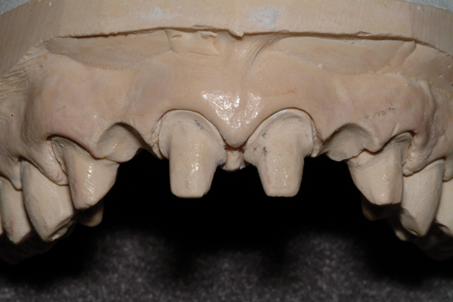

(9.) Ovate pontic sites created on the master cast by the laboratory.

Figure 9

After the abutment teeth are prepared and a provisional bridge is fabricated, an impression or intraoral scan is acquired, and the provisional bridge is cemented with a provisional cement. At the laboratory, an ideal ovate pontic site is created on the master cast, and the definitive prosthesis is fabricated.

A patient presented with two defective 3-unit fixed partial dentures spanning teeth Nos. 6 through 8 and teeth Nos. 9 through 11 (Figure 7). The defective fixed partial dentures were removed (Figure 8), an impression was made, and traditional provisional fixed partial dentures without ovate pontics were placed. After the impression was sent to the laboratory, the lab technician prepared ovate pontic sites on the stone cast (Figure 9) and fabricated the new definitive bridges. On the day of insertion, the provisional fixed partial dentures were removed (Figure 10), ovate pontic sites were prepared using a teardrop-shaped diamond bur (Figure 11), and the sites were sounded to confirm that there was at least 2 mm from the base of the pontic site to the alveolar bone (Figure 12). The fixed partial dentures were cemented, and the postoperative healing was uneventful (Figure 13).